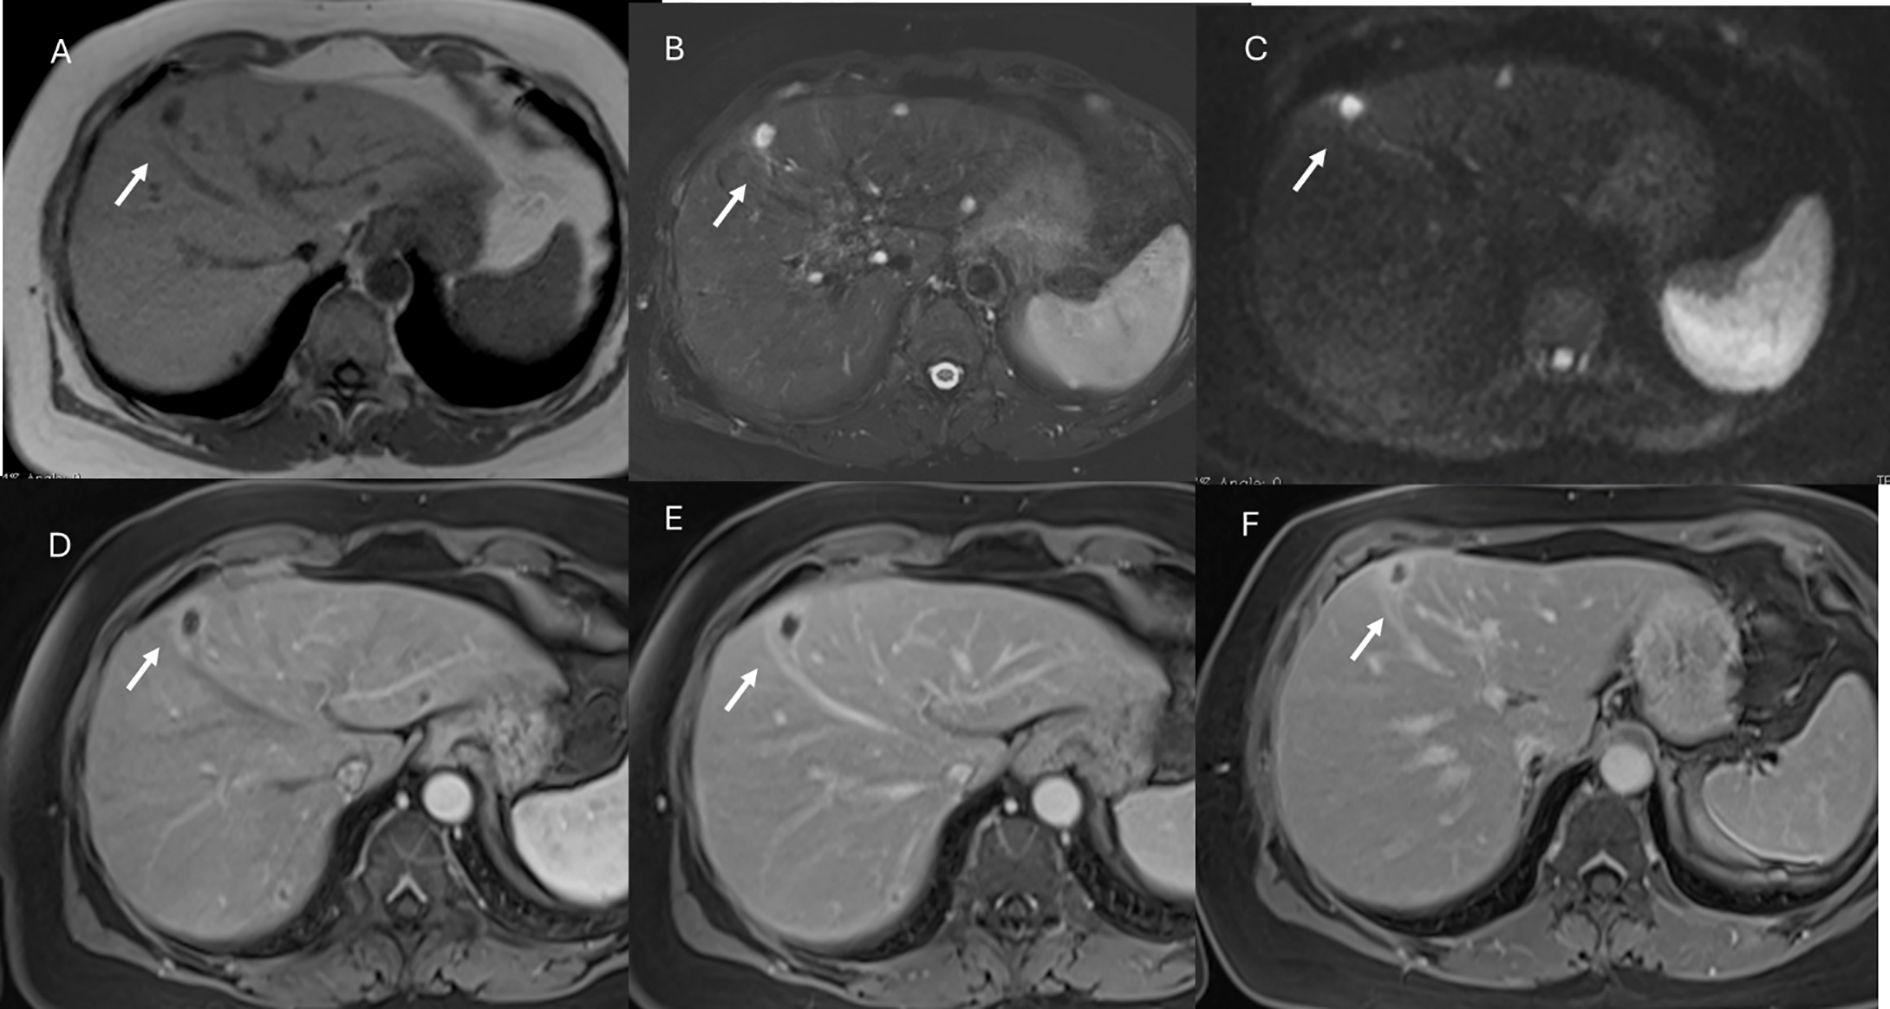

In the post-surgical setting, including transplantation, complications (Figure 9), technical success, new liver anatomy, presence of residual disease, or appearance of new lesions (Figure 10) must be evaluated. Attention must also be given to any extrahepatic findings (110).

Figure 9. MRI of liver abscess after surgical resection. The lesion (arrows) shows hyperintense signal in T2-W sequence (A), hypointense signal in T1-W sequence (B), restricted diffusion on b = 800 s/mm² (C), and hypointense signal on ADC map (D). This demonstrates that a benign lesion can also show restricted signal and hypointensity on ADC maps.

Figure 10. MRI assessment of residual disease after surgical resection. The lesion shows similar features to the patient in Figure 9, with hyperintense signal in T2-W sequence (A), hypointense signal in T1-W out-of-phase sequence (B), restricted diffusion on b = 800 s/mm² (C), and hypointense signal on ADC map (D). In this case, DWI is suggestive of residual lesion.